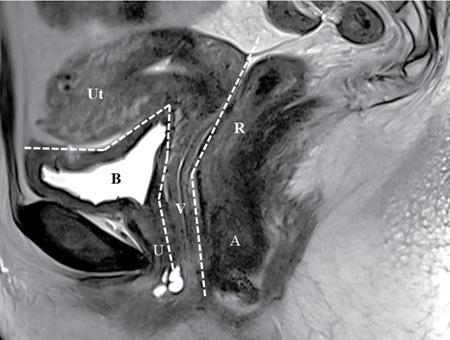

PELVIC FLOOR IMAGING – ANTERIOR AND MIDDLE COMPARTMENTS Anu Epean, Deepa Korula The term ‘Pelvic floor disorder’ refers to dysfunction of the pelvic floor musculature and connective tissues which provide support for the pelvic organs. This can produce a wide range of symptoms such a urinary incontinence, straining to void, dyspareunia, constipation, faecal incontinence and organ prolapse. The greatest risk factors for pelvic floor disorders are female sex and advanced age. Other risk factors include obesity, pregnancy, multiparity, smoking, connective tissue disorders. The pelvic floor is broadly divided into three compartments. The bladder and urethra form the anterior compartment. The vagina and uterus form the middle compartment and the posterior compartment comprises of the rectum and anal canal (Fig. 7.16.1.1). The attachment of the fascia, muscles and the ligaments to the bony pelvis form the support for these structures. From cranial to caudal, there are three layers which make up the pelvic floor – the endopelvic fascia, the pelvic diaphragm and urogenital diaphragm. This is the most cranial layer of pelvic floor, lying deep to peritoneum. It is a fine structure, comprising of a network of connective tissue which encases the pelvic viscera, provides support to the pelvic organs and maintains their anatomic relationship. There are several condensations of this fascia and ligaments which provide support in each of the pelvic compartments. In the anterior compartment, a fascial condensation called pubocervical fascia extends from anterior vaginal wall to the pubis. Tear in the pubocervical fascia can cause cystocele and urinary incontinence. There are three groups of ligaments which provide urethral support – periurethral, paraurethral and pubourethral ligaments. The periurethral ligaments arise from medial fibres of pubococcygeus and pass ventral to urethra. The paraurethral ligaments connect the lateral wall of urethra to periurethral ligament and pubourethral ligament connects the lateral wall of urethra to arcus tendineus. The urethra lies on a Hammock-like supportive layer of endopelvic fascia and anterior vaginal wall, which are stabilized by attachment laterally to arcus tendineus and levator ani (Fig. 7.16.1.2). In the middle compartment, condensations of the endopelvic fascia which attach the uterus to the lateral pelvic wall is called parametrium, which is made up of the uterosacral and cardinal ligaments. The uterosacral cardinal ligament complex supports and suspends the cervix and upper vagina above the levator plate. More inferiorly, the paracolpium attaches the vagina to the lateral pelvic wall. There are three levels of fascial support to the vagina: In the posterior compartment, the perineal body located within the rectovaginal septum supports ligaments and muscles and prevents abnormal widening of levator hiatus (Fig. 7.16.1.3). The rectovaginal fascia extends from posterior wall of vagina to anterior rectal wall. A tear in the rectovaginal fascia is the cause for an anterior rectocele. Arcus tendineus levator ani (ATLA) is formed by the condensation of the endopelvic fascia laterally, along the pelvic sidewall. This extends obliquely from inferior pubic symphysis to ischial spine and provides lateral support to the pelvic organs and attachment of the levator ani. Fascial condensations are not visualized on imaging; however, organ prolapse, due to deficiency in any of these, can be detected on MRI. The levator ani and the coccygeus muscles make up the pelvic diaphragm. The levator ani is the primary muscle of the pelvic diaphragm and is attached to the pubis and to the ATLA laterally on both sides. The slow twitch fibres of the levator ani continuously contract, maintaining tone to the pelvic floor and suspending the pelvic organs in the correct position. The two most important components of the levator ani are the iliococcygeus and puborectalis muscles. The iliococcygeus arises from external anal sphincter and has a curved shape, concave inferiorly. It fans out laterally to its insertion in the posterior part of arcus tendineus (Fig. 7.16.1.4A and B). Posteriorly, in the midline, condensations of ilococcygeus form a firm raphe anterior to coccyx called the anococcygeal ligament or levator plate. The pubococcygeus muscle is a component of the levator ani. It forms the anteromedial part and is a thick bundle of fibres arising from the pubis and anterior portion of arcus tendineus. It extends horizontally back to behind the rectum, medially forming the margin of urogenital hiatus (Fig. 7.16.1.5A). The anorectal and urogenital hiatus are closed by the contraction of the pubococcygeus muscle. This enables support during rest and in situations where the intraabdominal pressure is increased. The medial fibres of pubococcygeus, depending on their attachment to urethra, vagina, anus and rectum are termed as pubourethralis, pubovaginalis, puboanalis and puborectalis, collectively as pubovisceralis. The puborectalis forms a sling around the rectum (Fig. 7.16.1.5B). The muscles of the pelvic diaphragm are well delineated on MRI. The urogenital diaphragm or perineal membrane is the most caudal layer of the pelvic floor. It has a triangular appearance, extending from the pubic symphysis and the ischiopubic ramus to the posterior perineal body. It is ventral to the external anal sphincter and perineal body. It is attached to the surrounding structures such as the perineal body, external anal sphincter, vagina and the bulbocavernosus muscle. Imaging has an increasing role in the evaluation of pelvic floor disorders. Clinical examination alone has a low sensitivity and specificity for the detection of multicompartment involvement and organ prolapse. Imaging helps to detect involvement of multiple pelvic compartments and thus to plan surgery. Ultrasound, MRI and conventional imaging which includes voiding cystourethrography, evacuation proctography and dynamic cystocolpoproctography (DCP) are used to evaluate the pelvic floor. It is easily available, cheap and does not involve ionizing radiation. In the evaluation of the anterior compartment, ultrasound is more reliable than MRI. Transperineal ultrasound using 2D, 3D or 4D techniques along with dynamic imaging helps to evaluate pelvic floor dysfunction. Patient is placed in a dorsal lithotomy position for a transperineal scan although a standing position can also be used. Convex transducer (2–6 MHz) or endoluminal transducers (endovaginal/endorectal) maybe used. In a midsagittal translabial scan, the anatomic relationship of urethra, bladder, vagina, cervix and anorectum can be studied and the relative position of these organs determined by use of certain measurements. The bladder-symphysis distance (BND) is the distance between the bladder neck and lowest margin of symphysis pubis and demarcates position of the bladder neck. Measurement of BND is made at rest and during Valsalva manoeuvre and the difference in BND between the two, gives the measure of bladder neck descent. There are no definite values to indicate normal descent but there is a proposed cut off of 20, 25, 30 mm to indicate hypermobility (Fig. 7.16.1.6A and B). The proximal urethra rotates posteroinferiorly during Valsalva manoeuvre and this can be measured by the posterior urethrovesical angle (β) or the gamma angle. The posterior urethrovesical or retrovesical angle (β) is the angle between a line through the urethral axis and the line through the trigonal surface of the bladder and varies from 90–120 degrees normally. This may increase to 160–180 degrees and can be associated with funnelling of bladder neck. The gamma angle is the angle between a line through the inferior margin of pubic symphysis and the urethrovesical junction. This is seen on Valsalva manoeuvre or at rest in patients with stress incontinence (Fig. 7.16.1.7). Color Doppler can demonstrate urine leakage on performance of Valsalva or at rest. Other abnormalities that can be detected on transperineal ultrasound are cystocele, urethral diverticulum, Gartner duct cyst, foreign body or bladder tumour. 3D pelvic ultrasound is useful to evaluate pelvic floor dysfunction and to study the urethra, levator ani complex, paravaginal supports, prolapse and implant imaging. 4D ultrasound helps in real-time, dynamic imaging of pelvic floor. In the middle compartment, although uterine prolapse is often clinically evident, it can also be detected by ultrasound. Uterine prolapse can be also quantified by measuring maximum descent of uterus from the reference point which is the inferior margin of pubic symphysis. Ultrasound is also useful to evaluate for surgical planning in a large retroverted uterus with an anteriorly placed cervix causing voiding symptoms. MRI is useful in the evaluation of pelvic floor as it provides good anatomic detail about the pelvic floor muscles, ligaments because of its inherent superior soft tissue resolution. In addition, dynamic MRI yields functional information. MRI defecography is a dynamic study performed to study the posterior pelvic compartment but it also gives information about the anterior and middle compartments. It can be performed both with closed magnet and open magnet systems. The patient is positioned supine with phased array coil around pelvis in a closed magnet system. In an open magnet system, the patient is in a sitting and more physiological position; however, due to the lower signal to noise ratio and lower resolution, a closed magnet system is preferred. Bowel preparation with use of laxative on night before the scan is optional. Voiding prior to the study is encouraged since an overdistended bladder can cause misinterpretation of results. Presence of some urine in the bladder is however, helpful to detect anterior vaginal prolapse. Instructions are given to the patient, prior to the procedure, about the ‘rest’, ‘squeeze’, ‘strain’ and ‘defecate’ phases of dynamic imaging, to ensure that movement or lifting of the pelvis does not occur during these manoeuvres. The rectum is filled with up to 200 mL of ultrasound gel. The patient is made to wear an adult diaper and covered with an incontinence pad on the gantry. Vaginal gel, ∼50 mL maybe introduced since this helps to delineate anatomic landmarks and detect uterovaginal prolapse. Initial large FOV T1 localizer scans help to identify the midline sagittal section of pelvis. T2-weighted fast spin echo, high-resolution sequences in sagittal, axial, coronal planes are used to obtain anatomic detail. This is followed by dynamic imaging of the pelvic floor with use of steady state imaging sequences such as True fast imaging with steady state precession (TrueFISP Siemens) and balanced fast field echo (balanced FFE Philips). Steady state sequences have the advantage of short acquisition times and higher signal to noise ratio and hence useful to obtain rapid serial midsagittal images while patient performs ‘squeeze’, ‘strain’ and ‘defecates’. There are several points and lines for measuring and staging pelvic organ prolapse on MRI; however, the PCL line is said to have the highest interobserver and intraobserver reliability of MRI measurements compared to all proposed reference lines and is described below: Pubococcygeal line (PCL): defined as the line that connects the inferior portion of the pubic symphysis to the last coccygeal joint. The PCL is the most commonly used reference line for the assessment of pelvic floor disorders (Fig. 7.16.1.8).